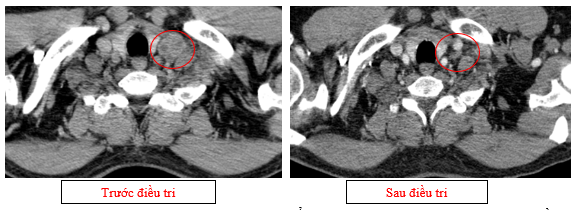

Hình 01: Nhiều hạch to trung thất, rốn phổi hai bên và hố thượng đòn có hoại tử trung tâm, hạch lớn nhất kích thước trục ngắn 22mm

Hình 07: Hạch thượng đòn trái giảm đáng kể kích thước, từ 22mm còn 7mm sau điều trị